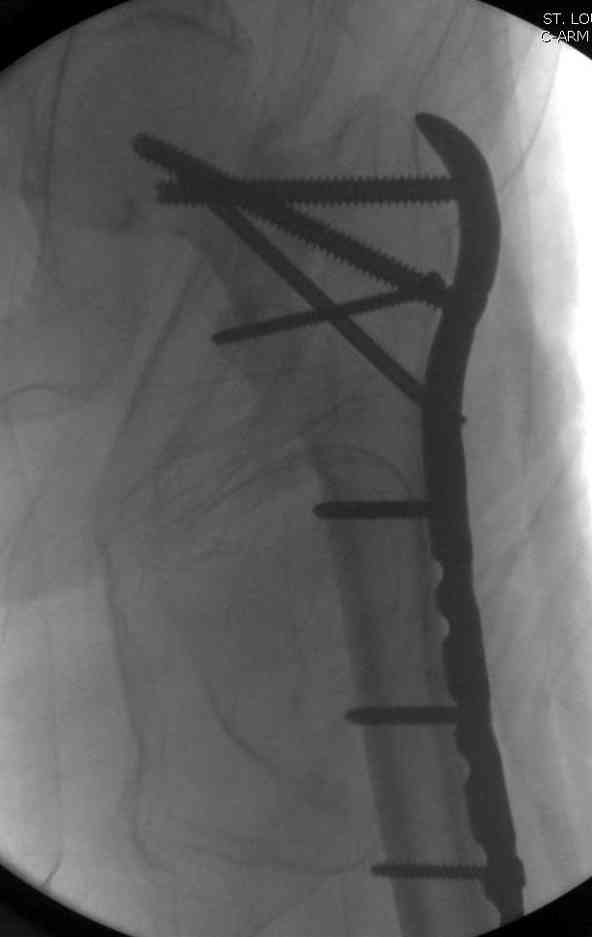

Из-за ослабленного латерального кортекса в проксимальной части бедра (прорезавшийся первичный неудачный штифт) штифт для фиксации не годится. Потом для установки современных блокирующих штифтов необходимы дополнительные оборудования и опыт применения.

Адекватная фиксация достигается длинным 95 градусным Blade Plate, где клинок пластины, связывая головку со средней трети бедра, создал бы условия для сращения.

Другой вариант пластины, это Synthes Proximal Locking Plate предназначенный для лечения прксимальных переломов бедра, где три шурупа: два 7.3 мм, введенных в головку под углом 95, 120 и 5.0 мм в 130 градусов, создают угловую стабильность.

Профилактику прорезывания шурупов в кости можно добиться введением в отверстие цемента, потом проведением шурупа, цемент, застывая, удерживает шуруп в правильном положении.